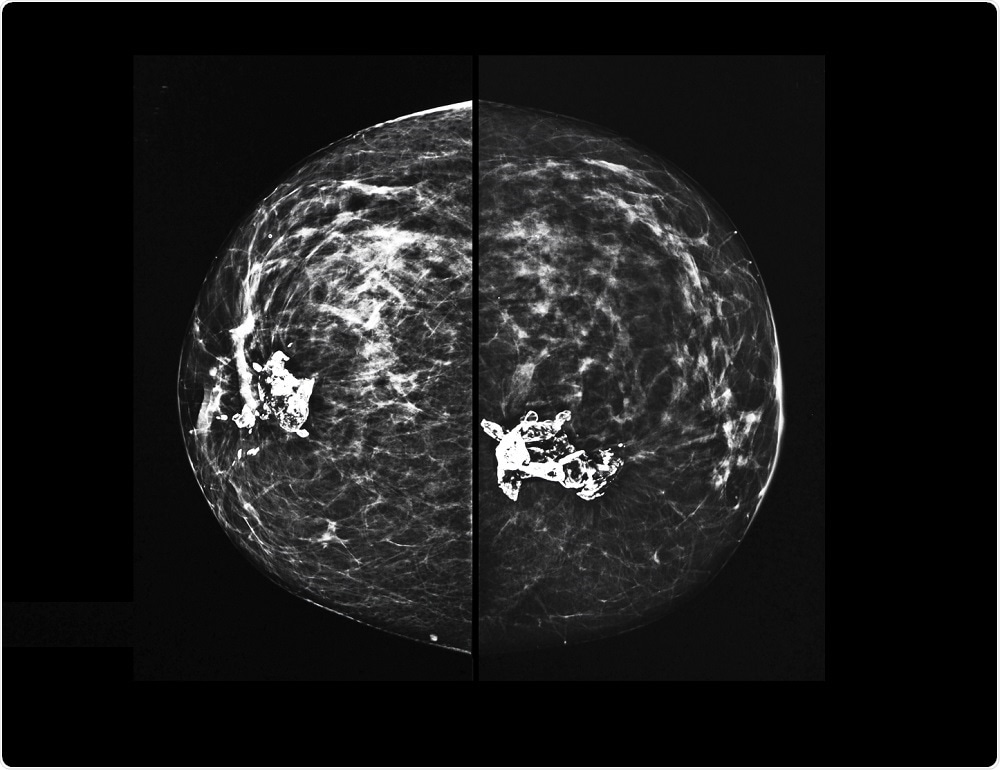

X-ray mammography of breast tissueSemnic | Shutterstock

DBT, commonly known as 3D mammography, takes X-ray images of the breast from several angles and builds a 3D image of the breast. It is reported to have a lower recall rate and a better ability to detect cancer when compared with 2D mammography.

In DBT, the X-ray moves in an arc over breast after it is compressed and captures images from several angles. These images are then digitized and synthesized into a 3D image of the breast.